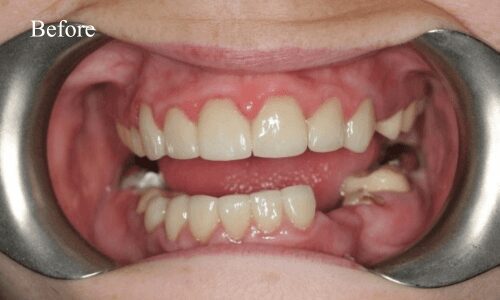

Full Mouth Rehabilitation

Full mouth rehabilitation or FMR is a restorative dental procedure which involves replacing all the teeth in the upper and lower jaws.This is a comprehensive treatment that combines general, cosmetic and restorative dentistry. This means you may have to get dental crowns, implants and whitening done at the same time to bring back the original strength, functionality, and aesthetic appeal of your teeth.